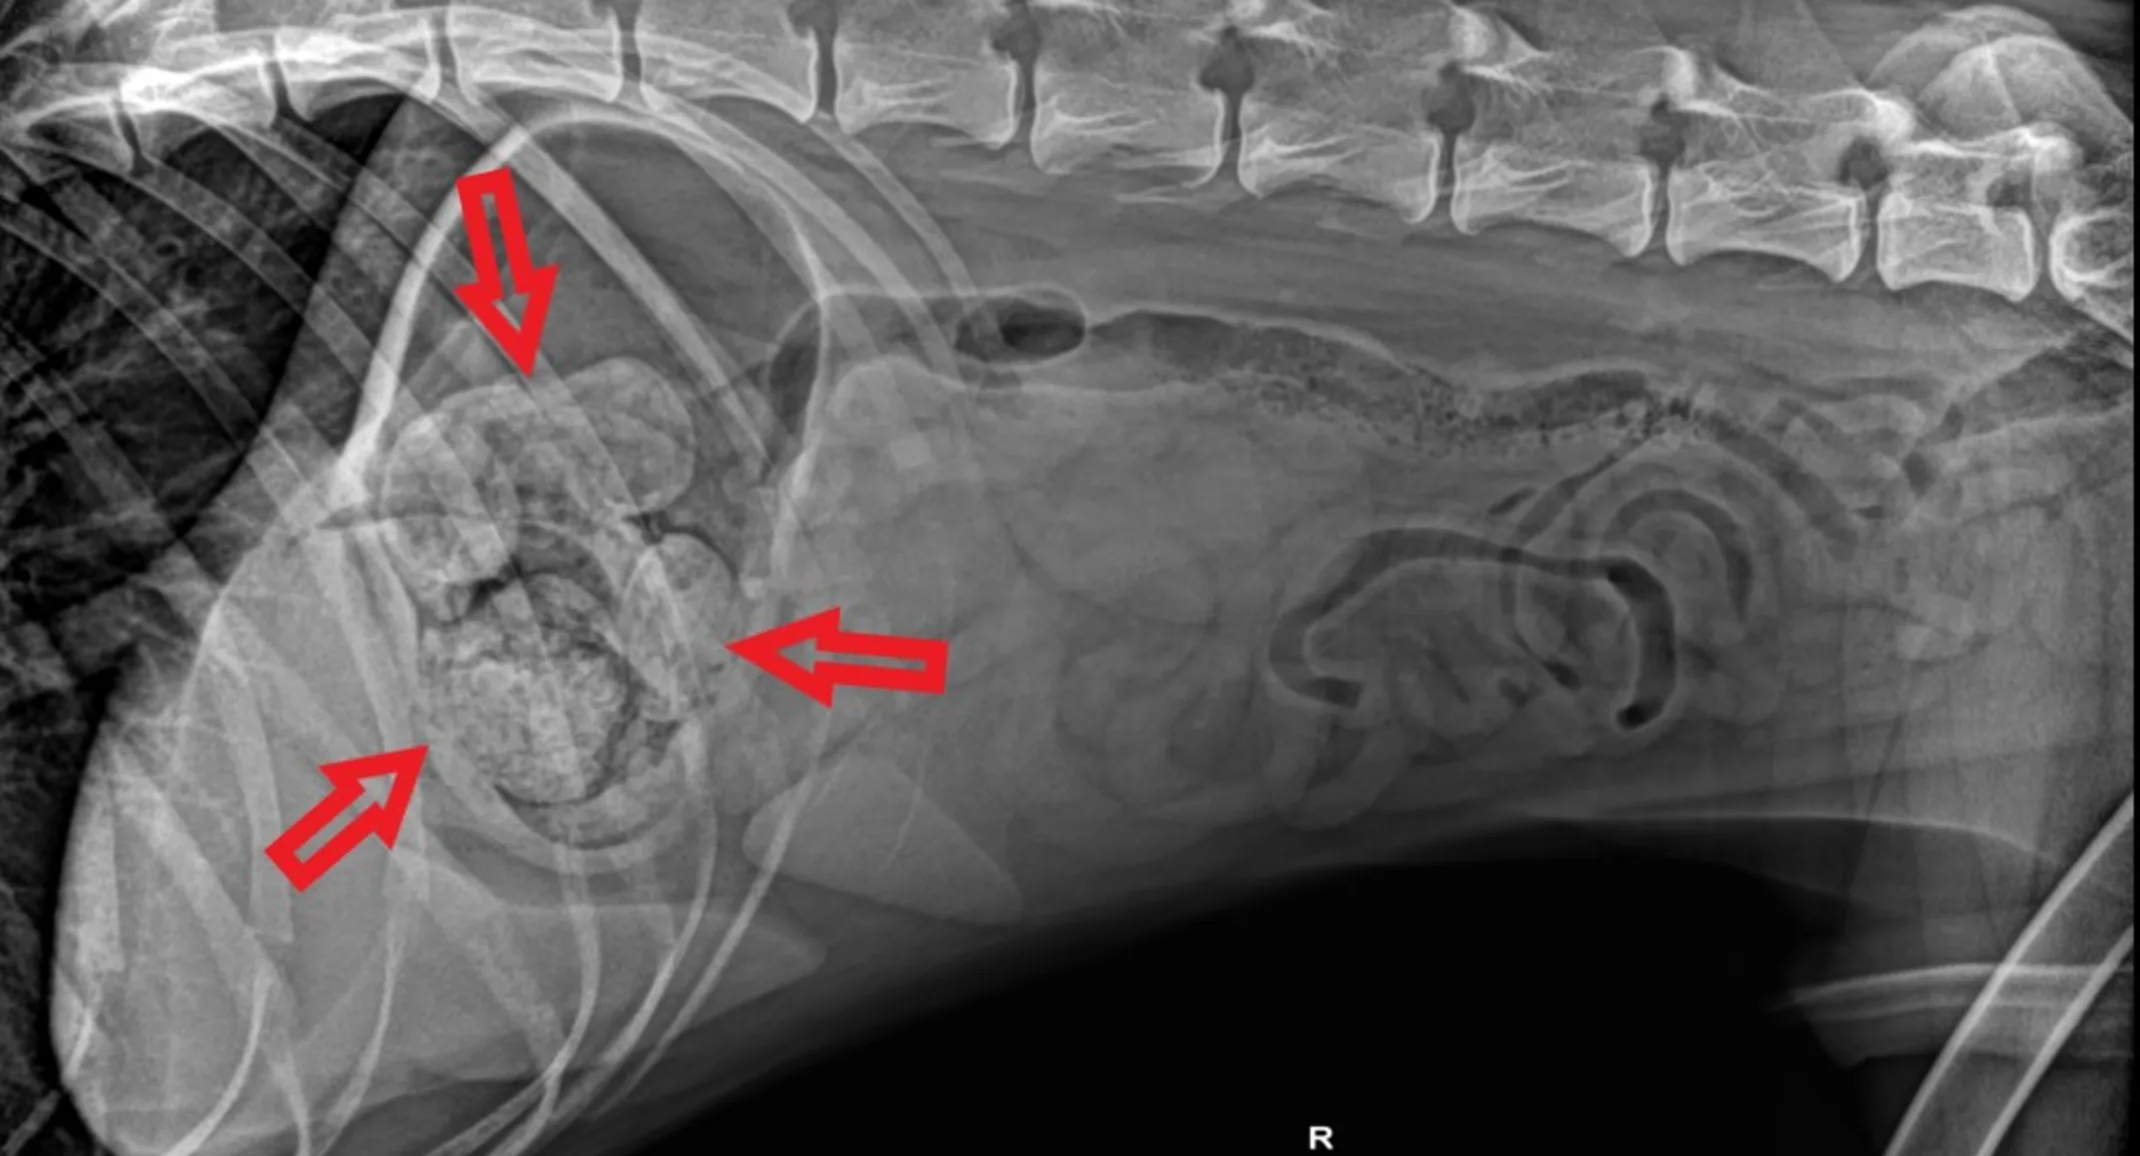

Attempts were made to make him vomit it up, but the toy did not come up and Saber soon stopped eating and became lethargic and sick. Saber presented to us 2 days after the toy was ingested since he was declining. Abdominal radiographs revealed an obvious object in the stomach (see the arrows on the x-ray) which showed the toy upside down with the 4 feet being visible, but the head was likely lodged in the pylorus which connects the stomach to the small intestines.